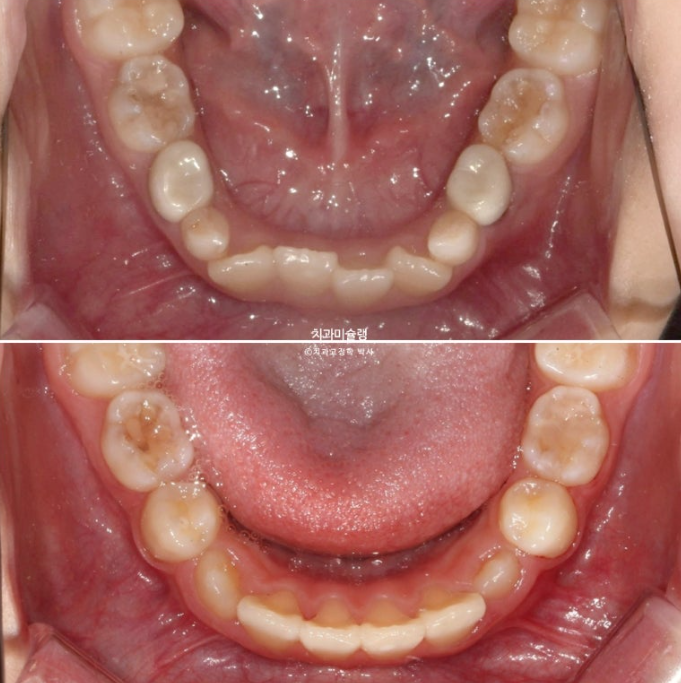

앞니 네개 중 옆 앞니 즉 측절치가 나올 공간이 좁습니다.

아래도 마찬가지 입니다.

앞니가 벌써 삐뚤삐뚤 합니다.

송곳니가 나올때는 어떻게 될까요?

덧니 100% 예약입니다.

어린이 교정은 악궁확장을 통해 이가 날 공간을 넓히는 과정이 동반이됩니다.

과개교합은 개선되었고 측절치 나올 공간을 악궁확장으로 미리 벌려줬기 때문에 측절치는 잘 내려왔습니다.

중심선 불일치 개선과 송곳니 나올 공간을 좀 더 확보하기ㅏ 위해서 추가장치 제작에 들어갑니다.

중심선은 잘 맞아졌고 과개교합은 더 개선이 되었습니다.

송곳니는 잘 올라오고 있습니다.

이제 전 후 비교 보겠습니다.

23.10~25.08